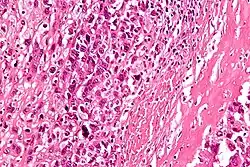

Intermediate-magnification micrograph of an osteosarcoma (center and right of image) adjacent to non-malignant bone (left-bottom of image): The top-right of the image has poorly differentiated tumor. Osteoid with a high density of malignant cells is seen between the non-malignant bone and poorly differentiated tumor (H&E stain). | |

Microscopically: The characteristic feature of osteosarcoma is presence of osteoid (bone formation) within the tumor. Tumor cells are very pleomorphic (anaplastic), some are giant, numerous atypical mitoses. These cells produce osteoid describing irregular trabeculae (amorphous, eosinophilic/pink) with or without central calcification (hematoxylinophilic/blue, granular)—tumor bone. Tumor cells are included in the osteoid matrix. Depending on the features of the tumor cells present (whether they resemble bone cells, cartilage cells, or fibroblast cells), the tumor can be subclassified. Osteosarcomas may exhibit multinucleated osteoclast-like giant cells.[22]